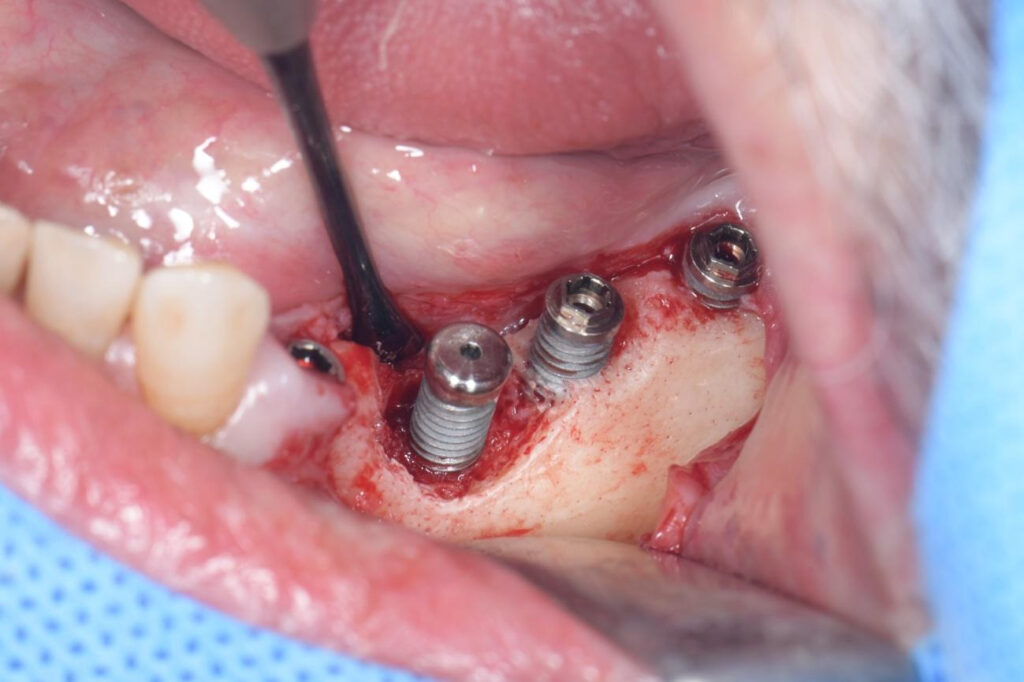

写真:インプラント周囲炎により溶けてしまった骨